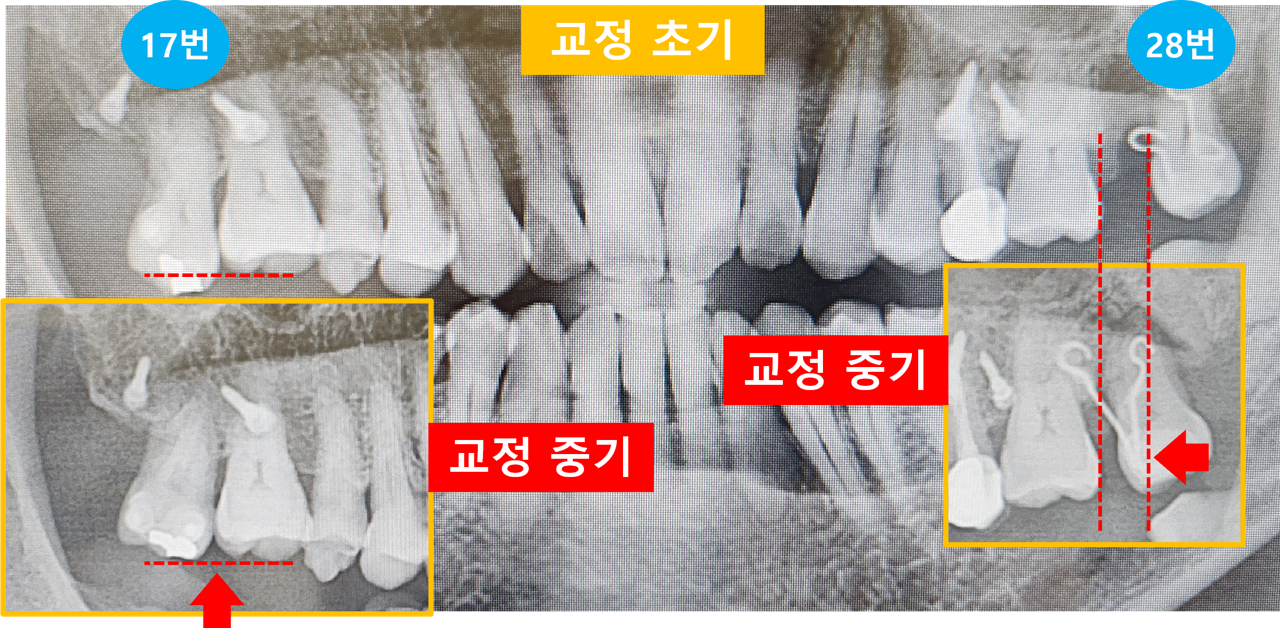

지난번에 찍었던 파노라마 사진을 보고 교정 전문의께서 상세한 설명을 해주었습니다.

제가 그냥 사진으로 비교해 봐도 확연하게 교정된 상황이 보이네요.

왼쪽 17번 치아는 16번 치아와 거의 높이가 같아졌습니다.

오른쪽 28번 치아는 빠진 27번 치아의 틈새를 거의 메꾸고 있는 것이 보입니다.

[교정 초기와 중기의 치아 위치 변경 모습]